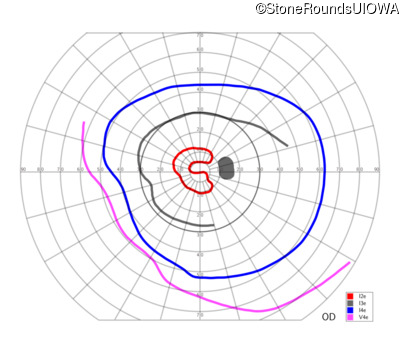

This 52 year old man had normal vision until his mid 30's when he began to have trouble distinguishing colors. the issuing 10 years he had a gradual loss of visual acuity accompanied by increasing photophobia.

| Age at visit: 55 years |

| Age at visit: 58 years |

| Age at visit: 61 years |

| Age at visit: 64 years |

| XL Cone and Cone Rod Dystrophy | RPGR | Gly1093 del2gGA | XL |